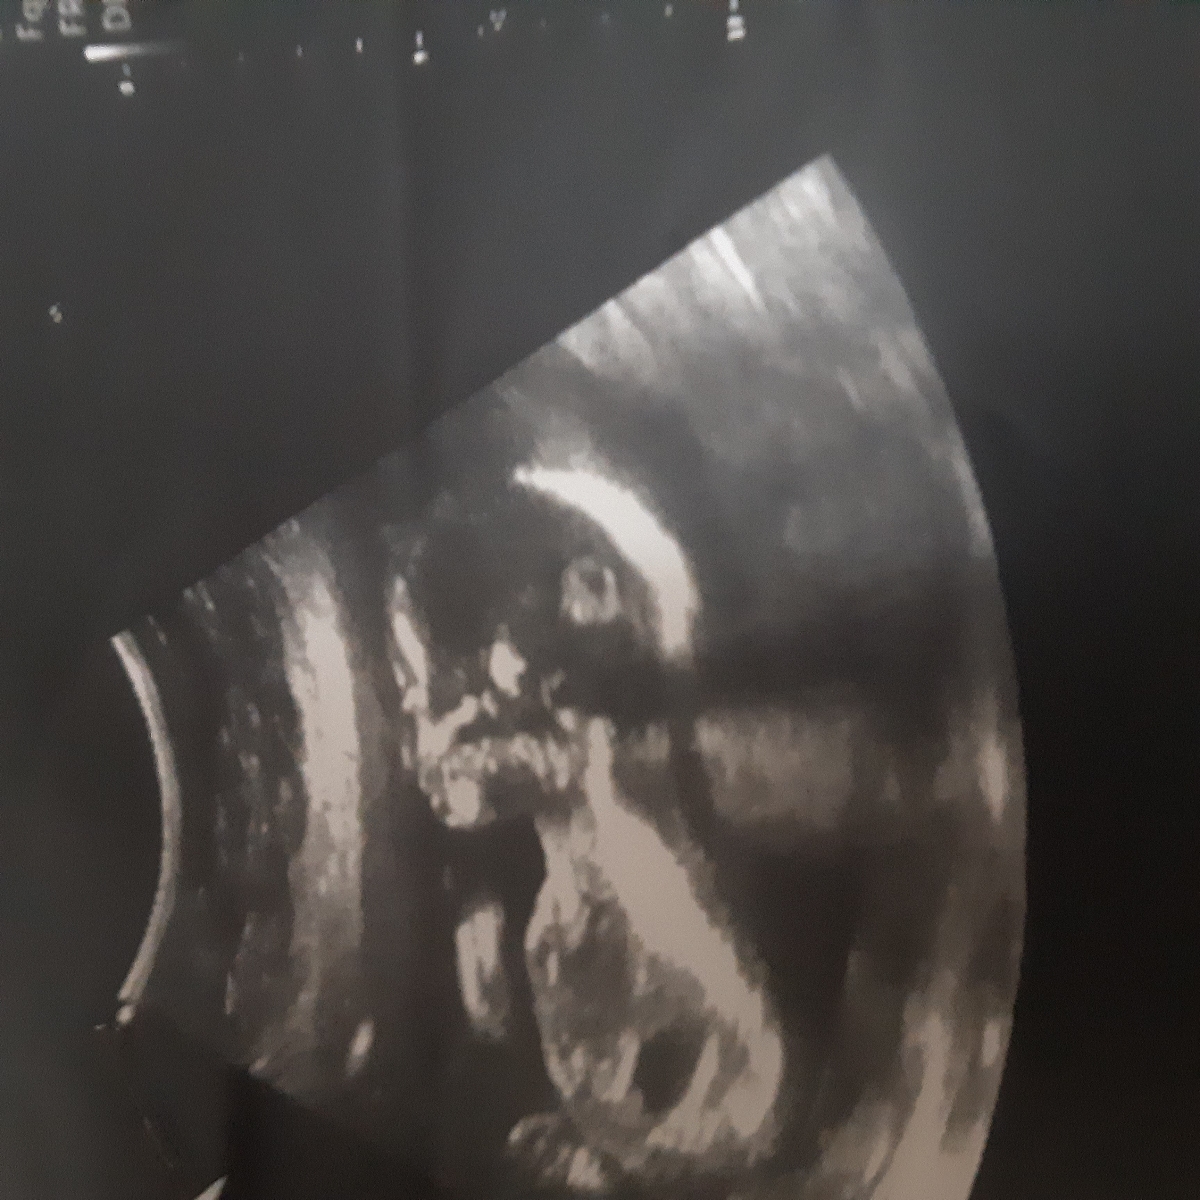

این چیه بنظرتون ؟؟

اینم بگیدددد دیگه😉😉

از روی ستون فقرات

بچهها ممنون الان من میگم عکس اول پسره دومی دختر؟؟ درسته بنظرتون